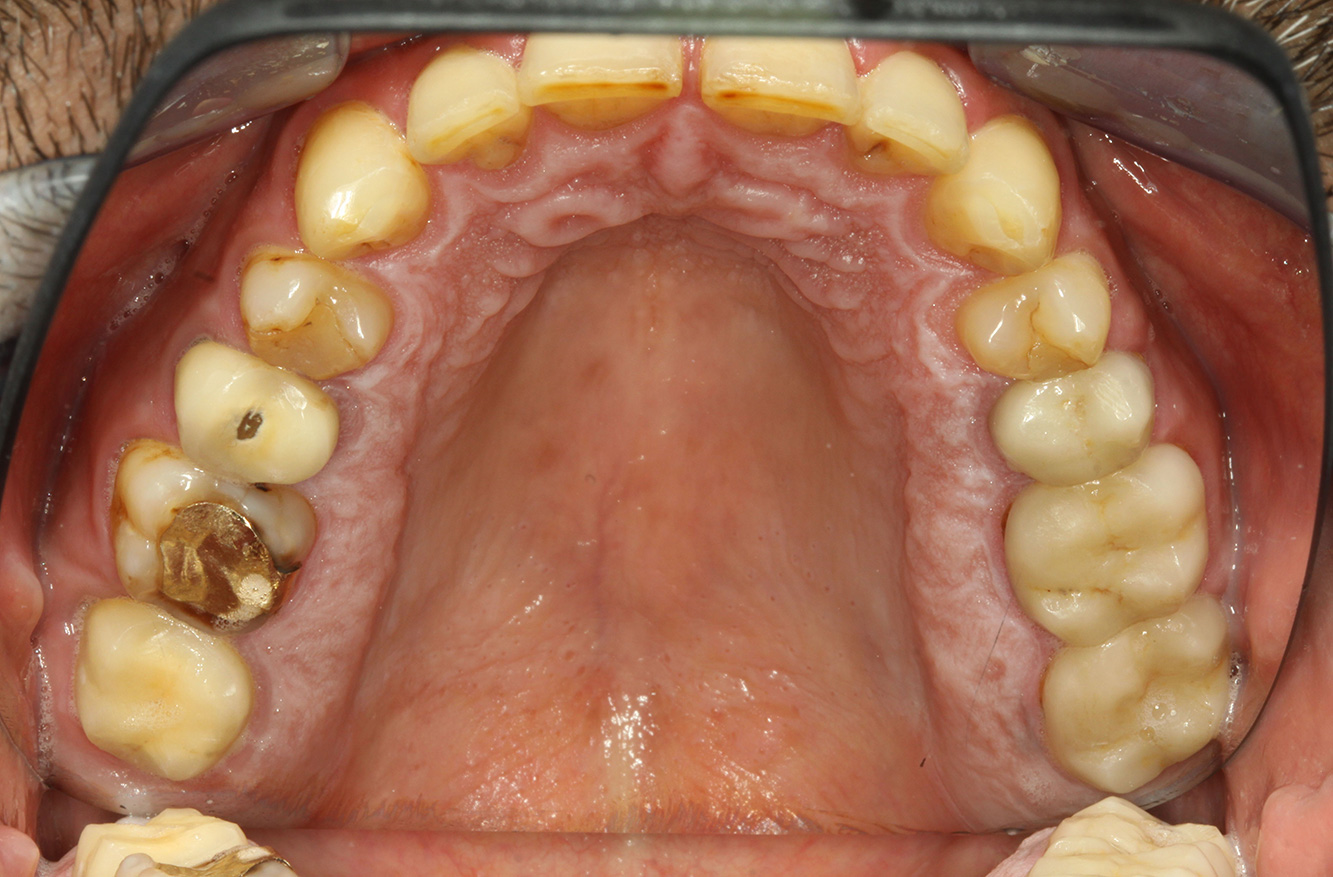

Der Patient ist 39 Jahre mit Z.n. Herzklappenersatz wegen Klappenfehlers und Endokarditis. Als Antikoagulans (Gerinnungshemmer) wird regelmäßig ASS 100 eingenommen. Aus dem Bereich Lebensstil ist die Ernährungsweise als kariesfördernd einzustufen, da mit hoher Regelmäßigkeit zuckerhaltige Lebensmittel sowie sechs bis sieben Mahlzeiten täglich verzehrt werden. Die Mundgesundheit des Patienten zeigt ein mittleres Kariesrisiko mit aktiven Läsionen. Das Parodontitisrisiko ist niedrig, es besteht eine Gingivitis. Es ergeben sich folgende Empfehlungen für die Prophylaxebehandlung.

Durch den Herzklappenersatz und die Vorgeschichte einer Endokarditis lässt sich ein erhöhtes Komplikationsrisiko ableiten. Um das Risiko einer erneuten Entzündung zu mindern, ist eine Antibiotikaprophylaxe zu empfehlen (z. B. 2 g Amoxicillin 1h vor Sitzung). Trotz der bestehenden Dauermedikation mit einem Blutverdünner, ist in der Prophylaxesitzung nicht mit einem erhöhten Blutungsrisiko zu rechnen.

Zur weiteren Unterstützung der Kariesprävention ist eine Fluoridierung, besonders um der Neuentstehung im Bereich der Restaurationsränder vorzubeugen, und eine Versiegelung der Wurzeloberflächen empfehlenswert. Beide Maßnahmen können die angegebene Temperatursensibilität der Zähne reduzieren.

Bedingt durch die aktiven Kariesläsionen und dem damit einhergehenden Progressionsrisiko ergibt sich ein verkürztes Recall-Intervall von drei bis vier Monaten.